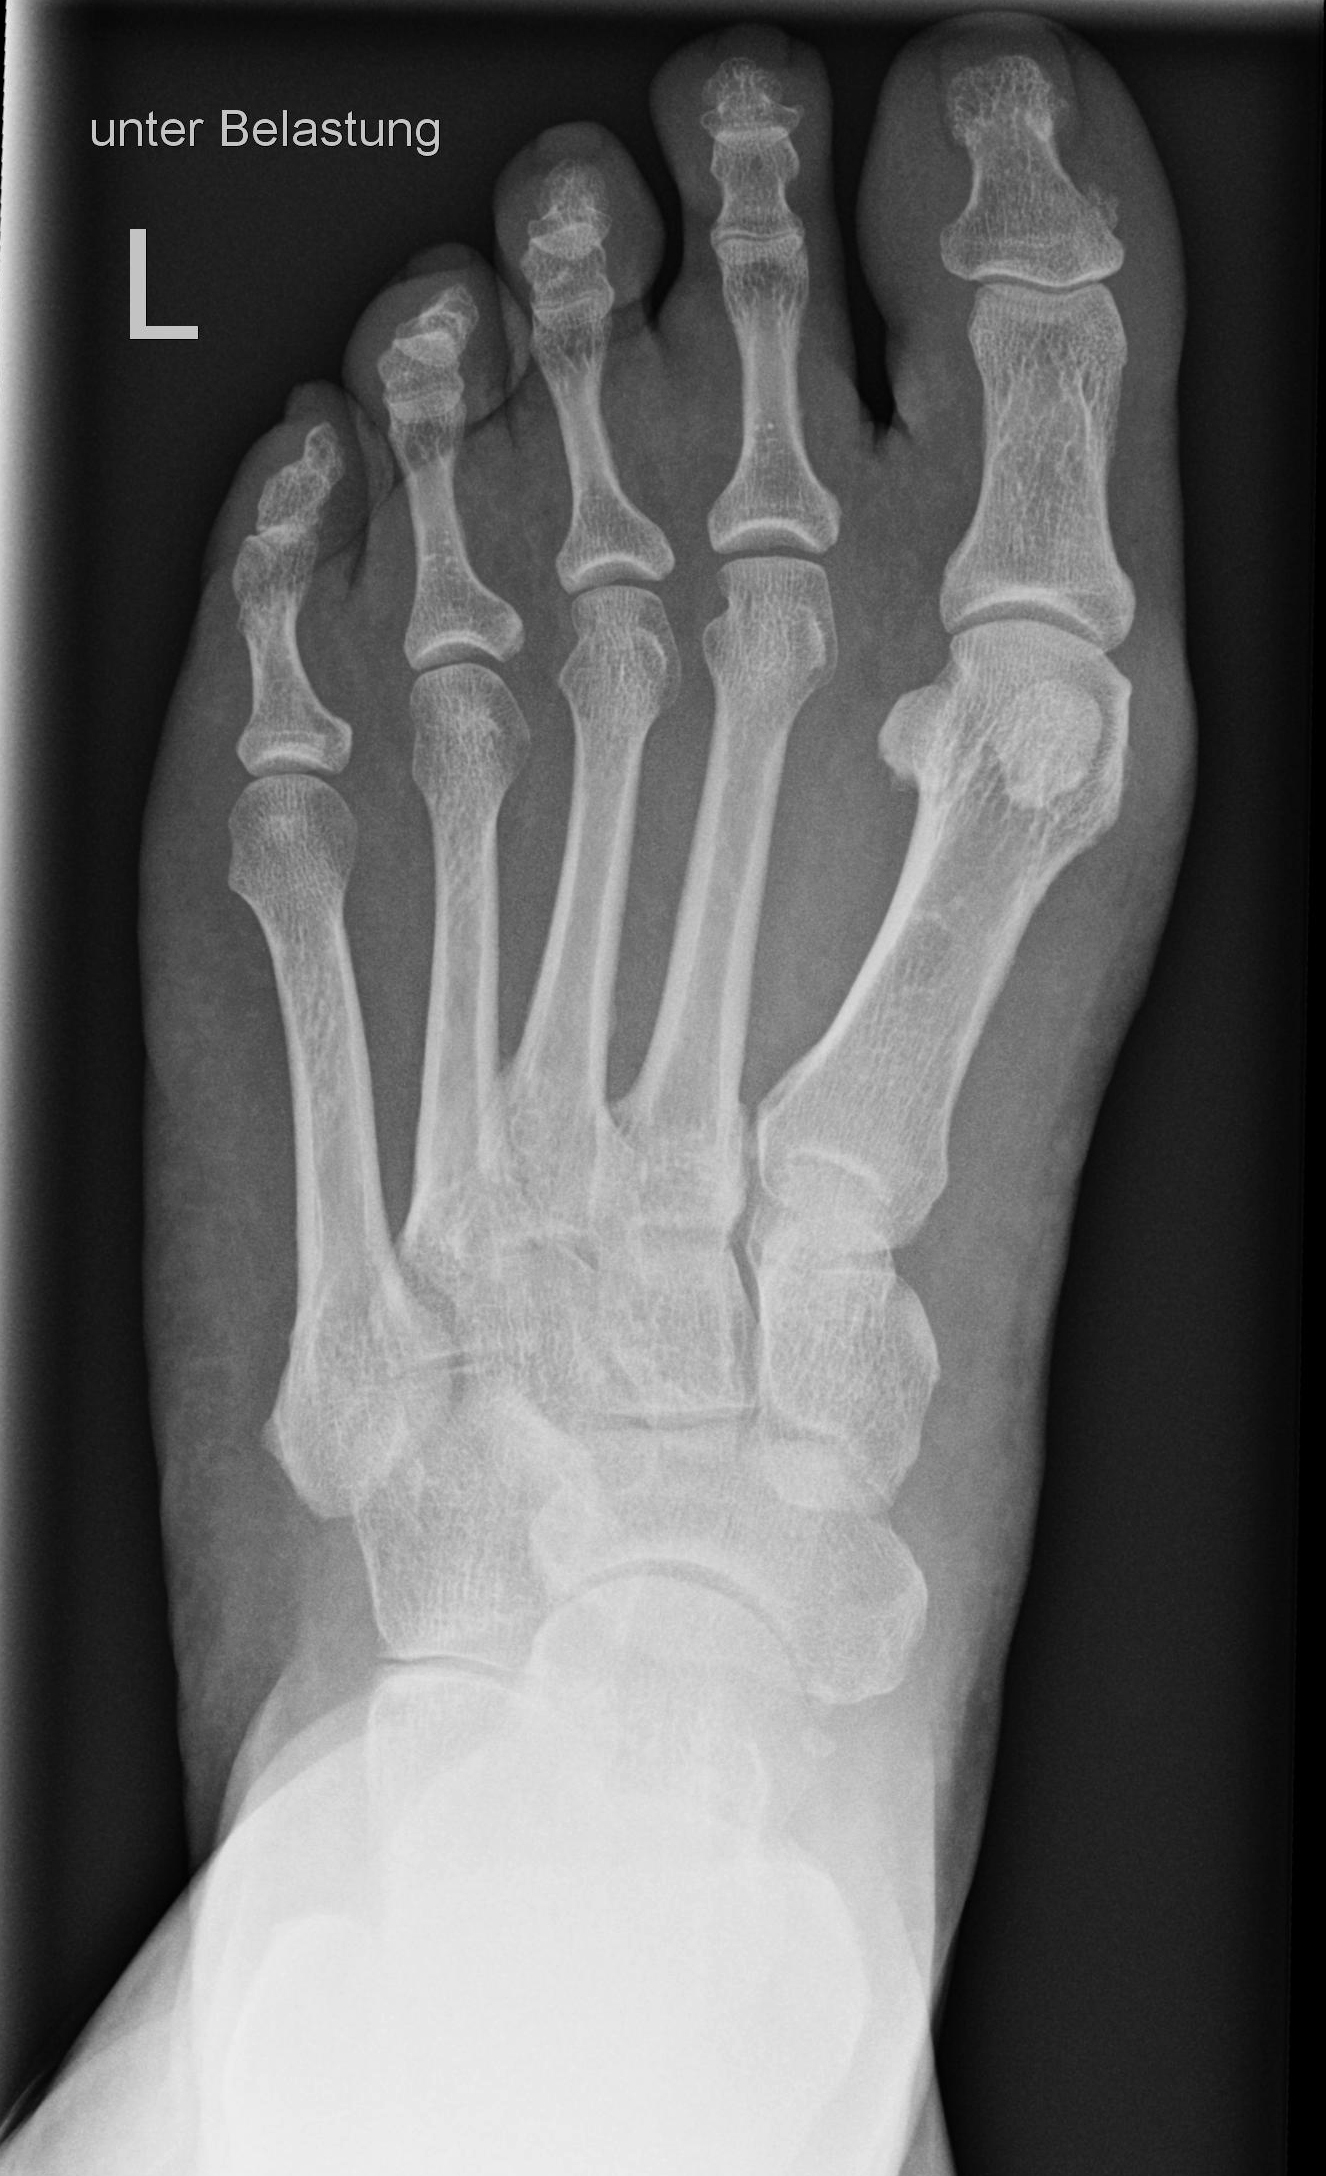

Fuß dorso-plantar (a.-p.) unter Belastung

Lagerung

stehend auf Bildempfänger

Knie leicht gebeugt und zweiten Fuß nach hinten versetzen um das Gleichgewicht zu halten

Es soll eine Belastung auf den Fuß erfolgen, aber nicht so, dass das Knie und die Bleischürze genau über dem Fuß schweben.

Zentralstrahl

Leicht Kippung zum Patienten auf Objektmitte

Einblendung

proximal bis einschließlich Malleolus lateralis

Anmerkung

Häufig passiert es, dass der Patient mit seinem Knie zu sehr über den Fußrücken kommt bzw. ins Lichtvisier. Deshalb mit dem zweiten Fuß einen leichten Schritt nach hinten machen und kontrollieren, dass das Knie und die Bleischürze nicht über dem Fuß schwebt.

Qualitätskriterien

Vollständige überlagerungsfreie Darstellung des ganzen Fußes a.p.